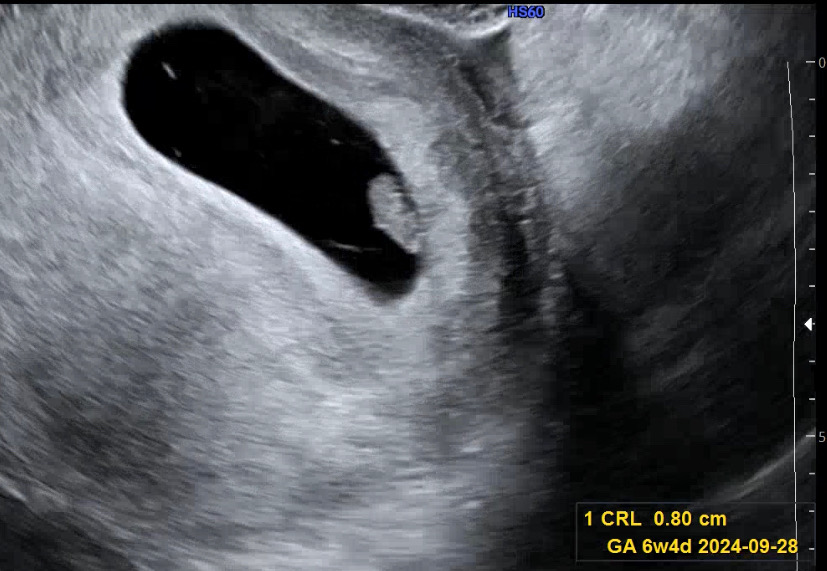

7주차 드디어 아기 심소 들었어요!

6주차 때 아기가 안보인다고 해서 남편이랑 마음 접고 병원 갔다왔는데 아기가 잘 크고 있다네요ㅠㅠ 4일동안 지옥과 천국을 오갔습니다. 6주차 6일째 아기가 안보인다는 결과 듣고, 희망을 버렸었고, 다른 산부인과 의사 소견을 들었을 때 유산가능성 90프로 이상이라고 해서 아에 마음을 접고 오늘 병원을 갔습니다. 그런데 네이버주수로 7주차 3일 오늘 아기 보고왔습니다. 저처럼 늦게 보이시는 분들도 있으실테니 기다려보세요! 아기가 잘 자라고 있을겁니다!! 4일 내내 아기가 안보인다는 카페글을 몇개를 읽었는지 모르겠네요..ㅠㅠ 이제 조금 마음 놓고 잘 수 있겠어요! 다들 화이팅입니다!!

저는 주수가 바꼈어요 ㅠ 처음 임신확인서 받았을 때랑 일주일 차이난다고 해서 지금 6주 4일차로 바꼈네요!